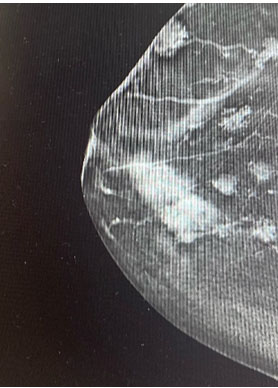

A 61-year-old female presented with a self-detected right breast lump associated with nipple puckering. Initial work-up investigations of ultrasound and mammogram revealed a 4 cm right breast lesion at 12 o’clock, 1 cm from the nipple (Figure 1) BIRADS 6 and a left breast lesion at 10 o’clock BIRADS 4. Core biopsies of bilateral lesions showed benign pathology of the left breast lesion and a 40 × 14 × 24 mm lesion of intermediate grade ductal carcinoma in situ in the right breast lesion with no evidence of invasive carcinoma. Her comorbidities of significance include a congenital cavernous hemangioma over right chest wall, past history of radiation exposure at age 3 due to childhood treatment of leukemia, hypertension, and benign liver cysts. Her risk factor profile included a family history of breast cancer (mother and maternal aunt), no breastfeeding history and a hysterectomy and oophorectomy after diagnosis of cervical cancer.

Figure 1: Mammogram revealing a 40 mm. Right breast lesion with extensive cavernous hemangioma.